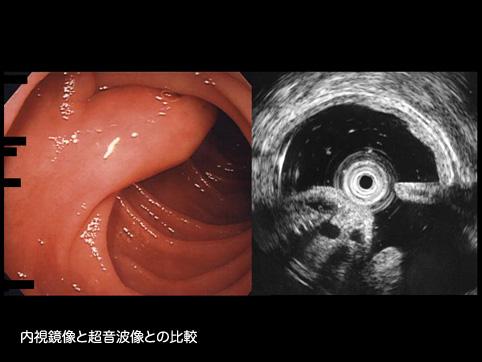

疾患(病理主体)の分類腫瘍様病変/過形成ポリープ

部位(臓器別)十二指腸/下行脚

検査方法エコー

腫瘍の肉眼分類0型(表在型)/I型(Ip)

病変の最大径(ミリ)15〜19